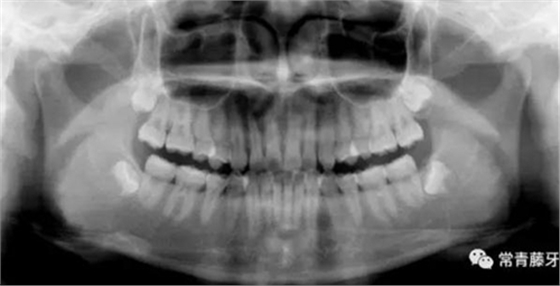

全口曲斷顯示A1B1根尖存在吸收。

頭影測量顯示為骨性Ⅱ類低角患者。